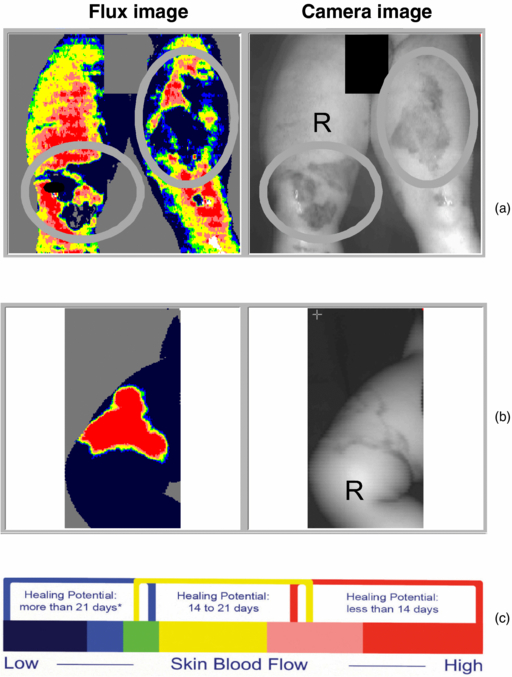

It is important clinically to determine if a burn is deep or superficial as this affects the choice of treatment. A deep burn usually requires grafting, whereas a superficial burn with skilled conservative management can heal on its own within 21 days without costly surgery. In deep tissue burns, the dermal layers and associated vasculature are damaged and so the hyperaemic blood flow response in normal wound healing is disrupted. A reliable hyperaemia will be present or absent after about 48 h post burn for superficial dermal or deep dermal burns, respectively, and use of LDPI to assess this (figure 4) has been validated, until 5 days post burn, by Monstrey et al (2011) and Pape et al (2012). LDPI can detect the microvascular blood flow in the dermis and, when used within this timeframe, can detect the presence of hyperaemia and thus give objective evidence for a burn being classed as deep or superficial (Hoeksema et al 2009, Pape et al 2012).

Figure 4. (a) Deep dermal burns can be clearly seen in the circular regions of interest on the legs and (b) a superficial dermal burn with (c) scale guide indicating the healing potential in days. (Courtesy of the Department of Plastic & Reconstructive Surgery, Ghent University Hospital.)

Standard image High-resolution imageLDPI is now a widely accepted tool to assess burn depth, with an ever-increasing body of evidence to support its use, as described in reviews (Devgan et al 2006, Sainsbury 2008, Monstrey et al 2008, Sharma et al 2011). The National Institute for Health and Clinical Excellence (NICE) (2011) provided evidence of clinical benefit and cost saving when LDPI (specifically for the Moor Instruments moorLDI2-BI imaging system) was used to guide treatment decisions for patients in whom there was uncertainty about burn depth and healing potential. This was a reliable endorsement to support both the clinical efficacy and health economics of the technology.